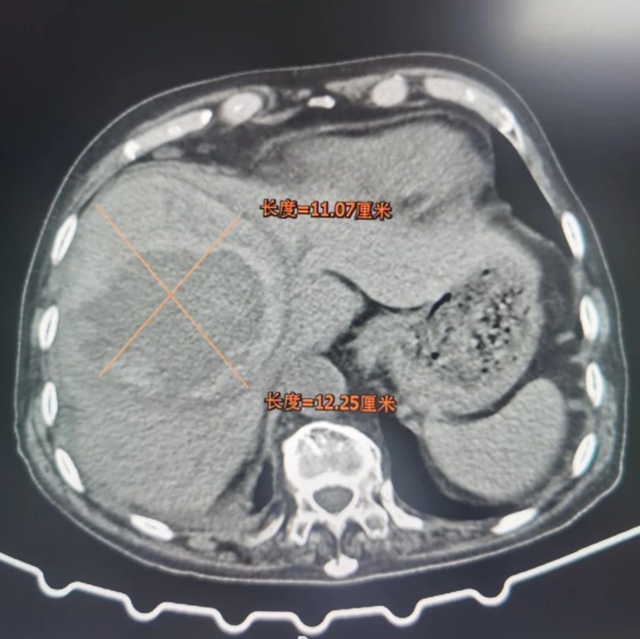

70多岁的喻大爷体检时发现肝脏占位性病变,刚开始并没有在意,谁知没过多久大爷开始出现肝区(右季肋部)疼痛,熬了几天实在受不了,喻大爷赶紧来到西南医科大学附属中医医院肝胆病科就诊。完善相关检查后,发现肿瘤达11.07cm*12.25cm,肿瘤指标略偏高,进一步经肝穿刺病检,最终确诊为原发性肝癌。

考虑到大爷肿瘤较大,且年龄较大,整体身体状态较差,肝胆病科团队为其实施了“肝动脉造影+灌注化疗栓塞术”,术后在西医治疗基础上口服中药制剂和枢消积丸,随后加入科室四川省科技厅重大专项研究中进行规范随访。4个月复查,喻大爷肿瘤已明显缩小至7.75cm*8.24cm。

术前

术后

对比肿瘤明显缩小